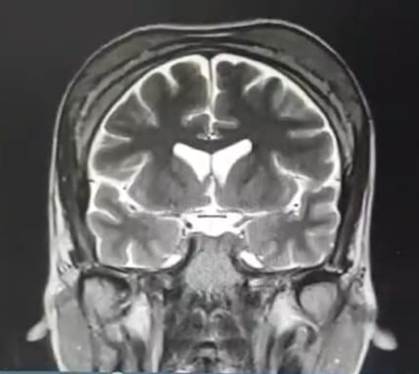

La exploración física reveló protrusiones óseas en la región frontoparietal y en la arcada maxilar superior, sin compromiso neurológico evidente. Se realizó resonancia magnética de encéfalo (Figura 2), que evidenció infiltración ósea difusa con engrosamiento cortical del hueso frontal y maxilar. No se identificaron lesiones osteolíticas focales en ese entonces.

Figura 2. Resonancia magnética cerebral en secuencia coronal T2 donde se evidencia infiltración ósea difusa en calota craneana, con engrosamiento de la tabla interna y externa. No se observa compresión de estructuras intracraneales.